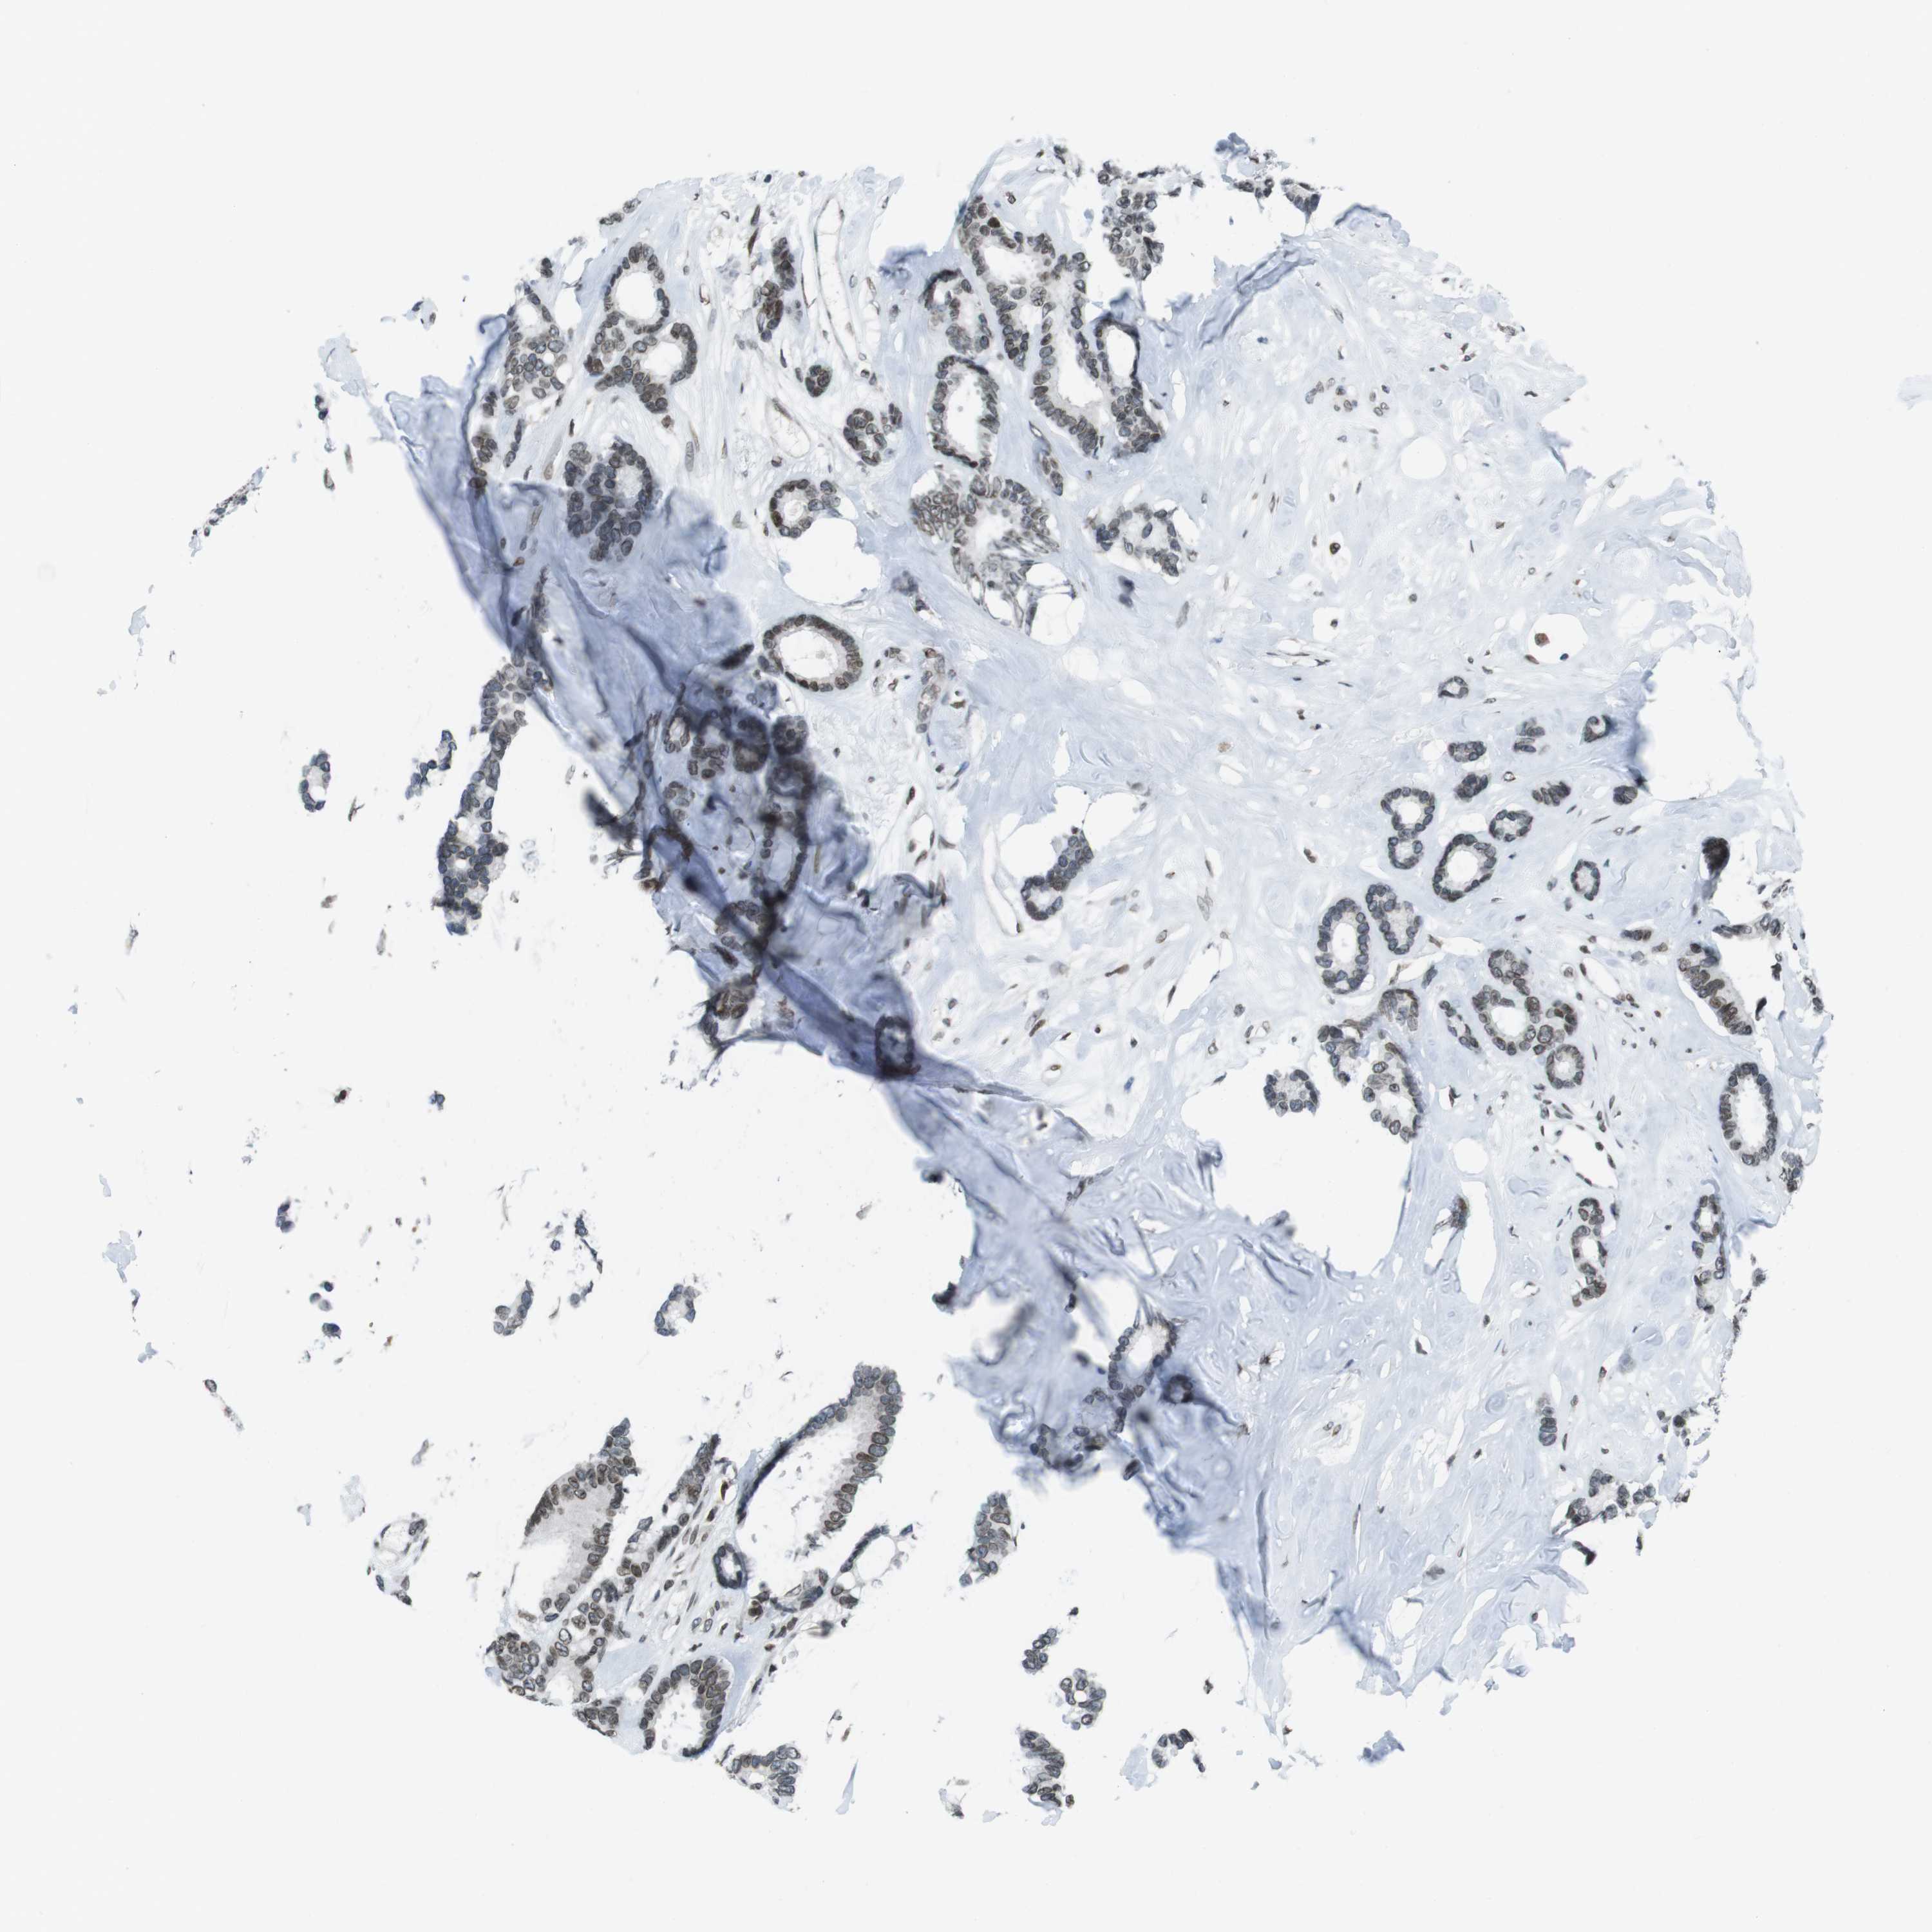

BRCA TCGA BRCA VALIDATION PROTEIN EXPRESSION